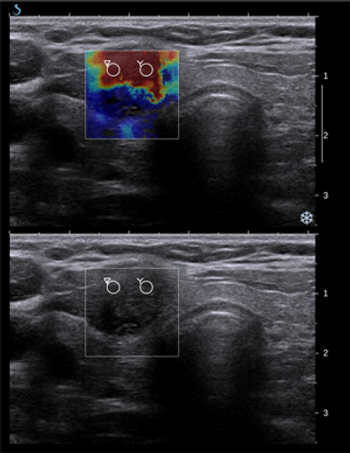

Two studies presented at the 2014 ASH Meeting addressed whether an interim PET scan during and after an initial therapy can help guide treatment.